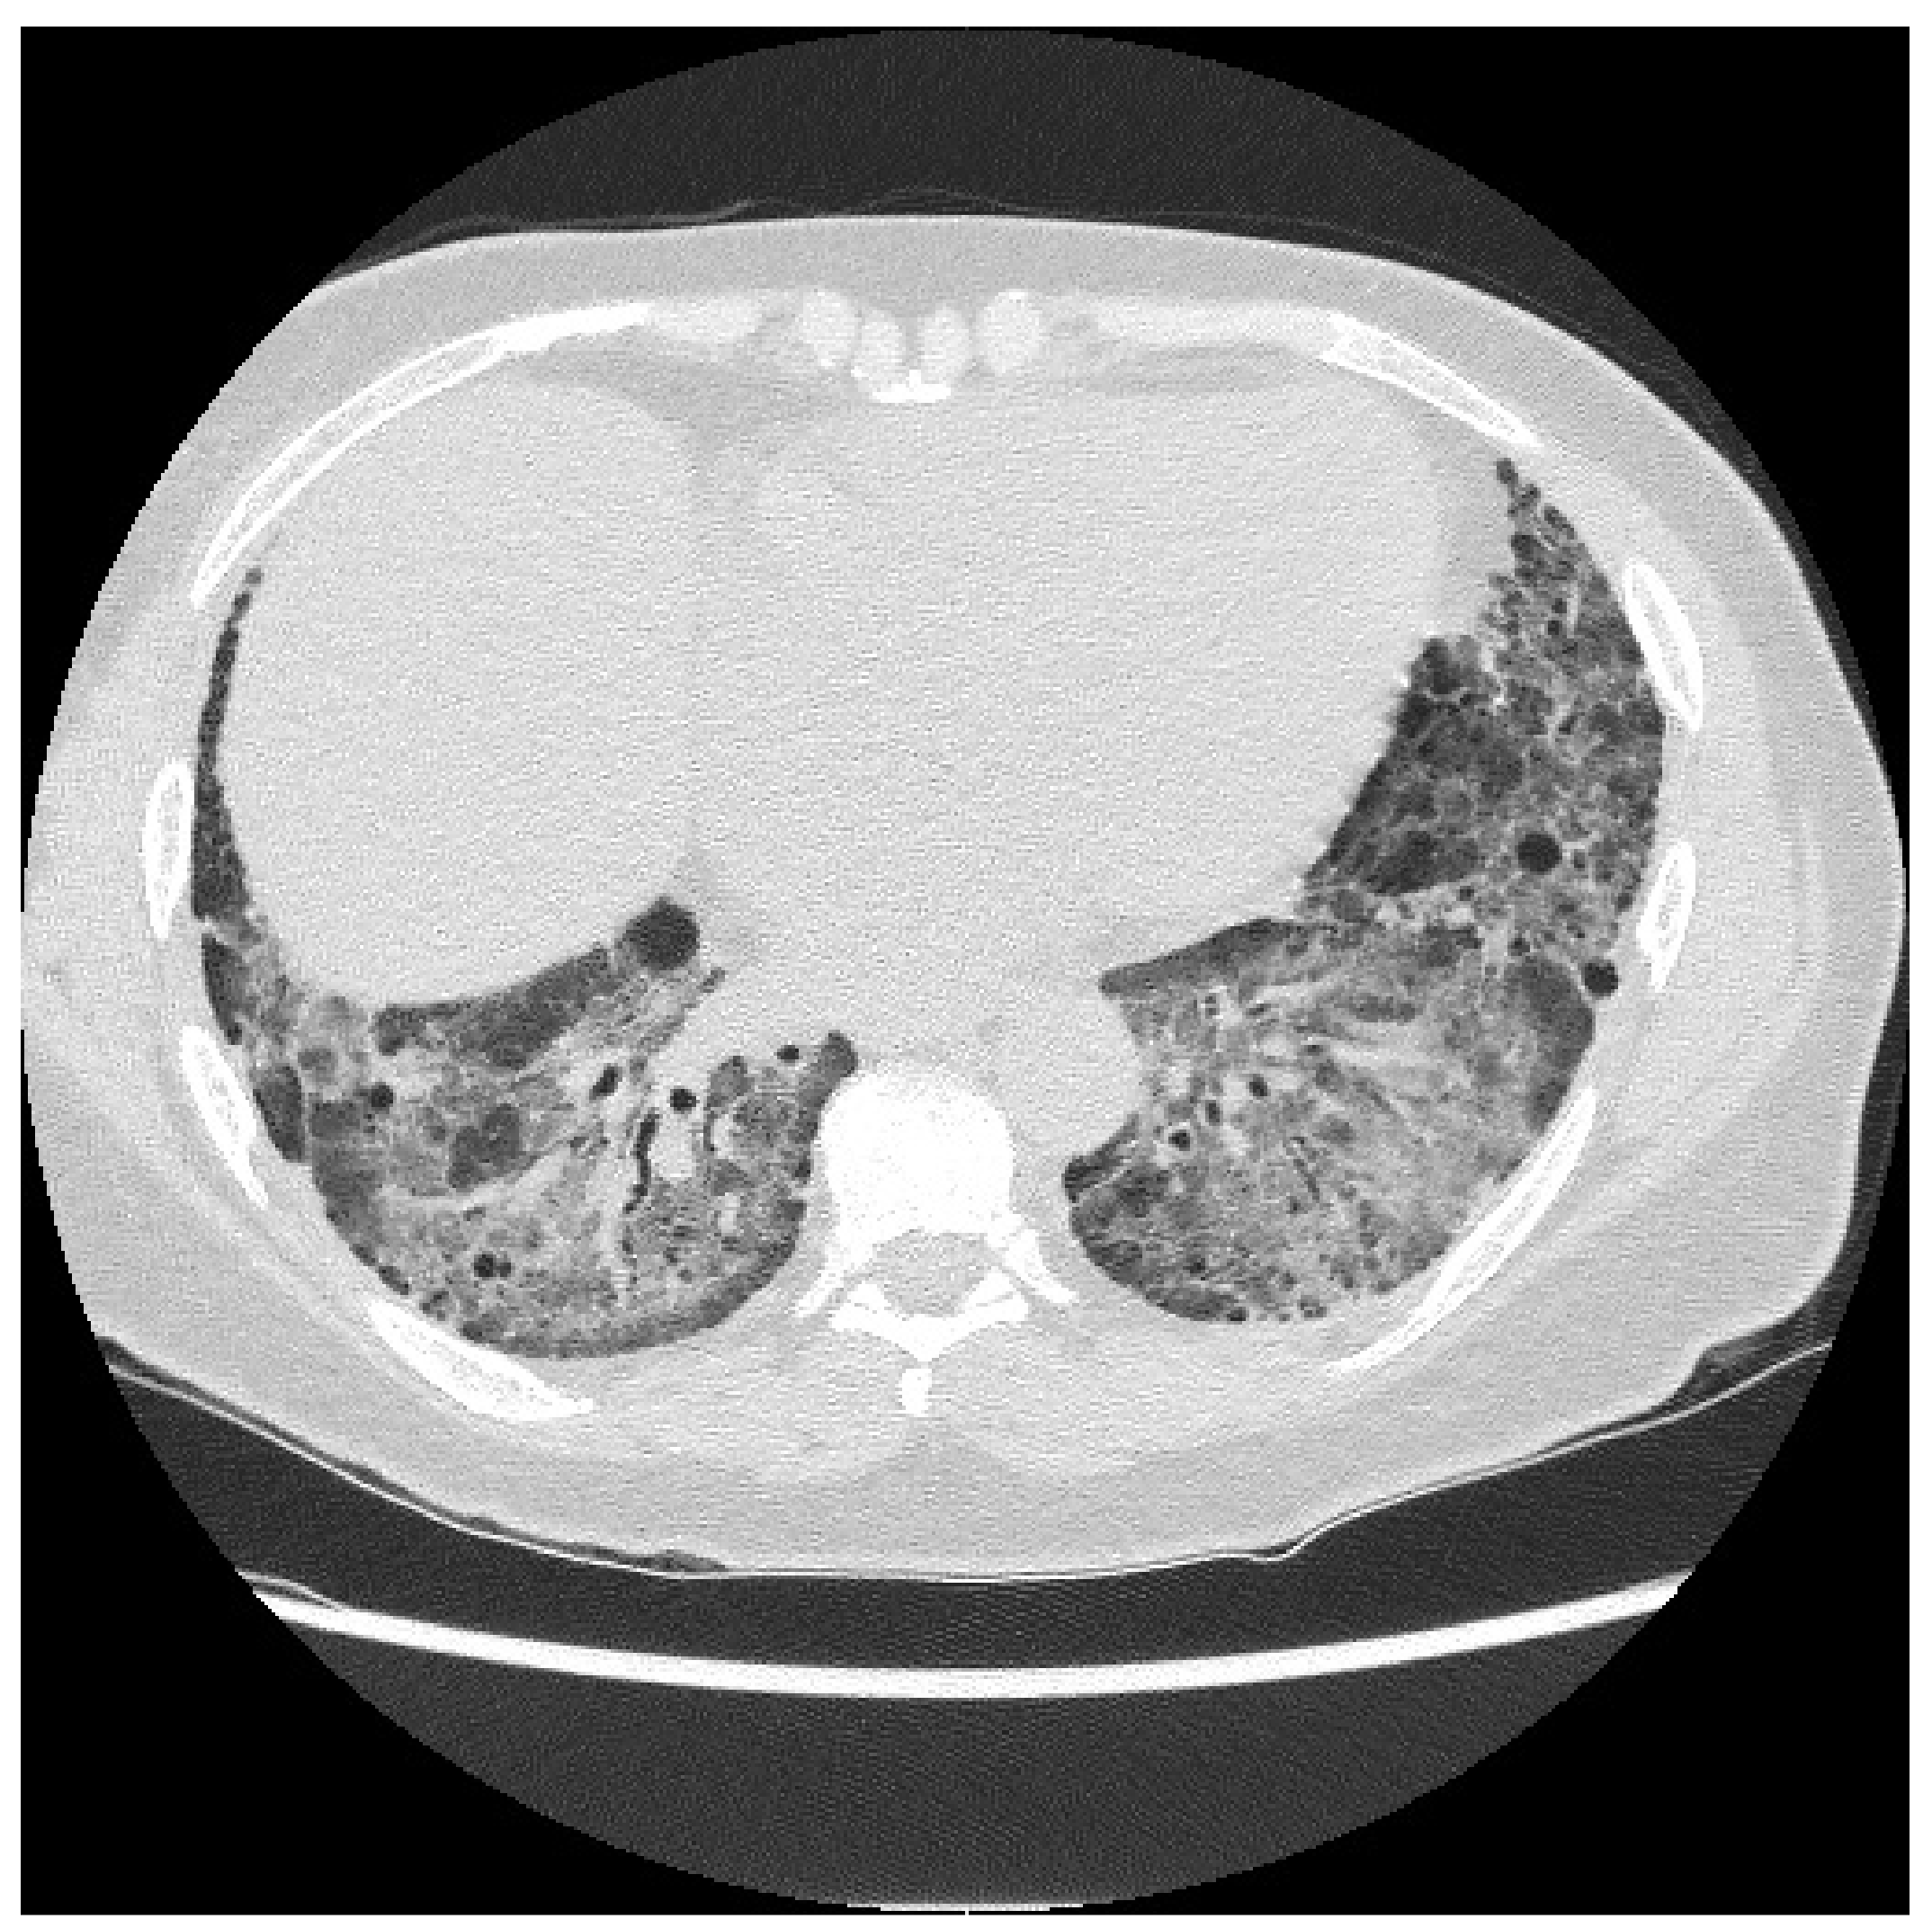

2.1. Case Report 1

6.2. Histopathologic and Radiographic Findings in Myositis-Associated ILD